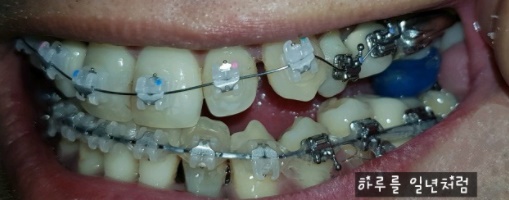

너무 많이 뒤죽박죽 되어 있었던 내 치아들을 얇은 와이어줄과, 굵은 와이어 줄을 교체하 가면서 치아들을 조금씩 자리잡아 갔었고,

위 사진과 비교해 보면 치아들이 상당히 가지런히 된 모습이다.

그렇게 교정 시작한지 2년6개월이 흐르고 나서 드디어 끝이 보였다...